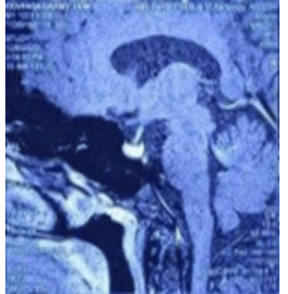

MRI (Magnetic Resonance Imaging) brain revealed

encephalomalacia with adjacent gliosis in right frontotemporal region, T1

isointense and T2 hypo-intense lesion in the sella of size 9.1 × 8.8 × 8.6 cm.

On dynamic contrast, it shows hypo-enhancement and delayed homogeneous

enhancement suggestive of pituitary microadenoma (Figure

2).

Figure 2: MRI brain with contrast showing homogeneous

enhancement of pituitary